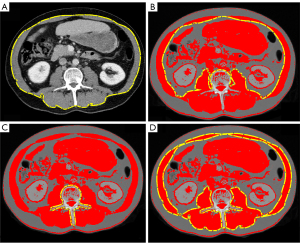

Axial CT slices (slice thickness 5 mm) at the height of the third lumbar vertebra (L3) on portal venous CT scans were exported and further processed with the open-source software ImageJ (National Institutes of Health, Laboratory for Optical and Computation Instrumentation). Regions of interest were defined along the outer abdominal muscle parameter (Figure 1A), inner muscle parameter (Figure 1B), and the circumference of L3 (Figure 1C). The most commonly used muscle-specific threshold of −29 to +150 Hounsfield units (HU) (16) was applied and the SMA calculated according to Gomez-Perez et al. (22). The SMI was then given by SMA/body height2 (cm2/m2). After application of the muscle-specific threshold, the MRA of the whole abdominal muscle in HU (Figure 1D) was noted.